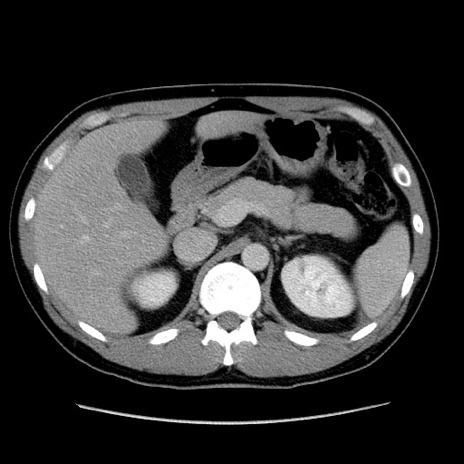

症例4(横断像)

【症例】30歳代男性

【主訴】腹痛、嘔吐

【現病歴】昨晩から突然の腹痛あり、その後嘔吐、軟便も出現。腹痛が改善しないため救急搬送となる。2日前にしめ鯖の食事歴あり。

【身体所見】意識清明、苦悶様、BP 135/90mmHg、BT 35.7℃、腹部:平坦、やや硬、心窩部〜臍部に自発痛、圧痛あり、筋性防御+、反跳痛-

【データ】WBC 8100、CRP 0.57